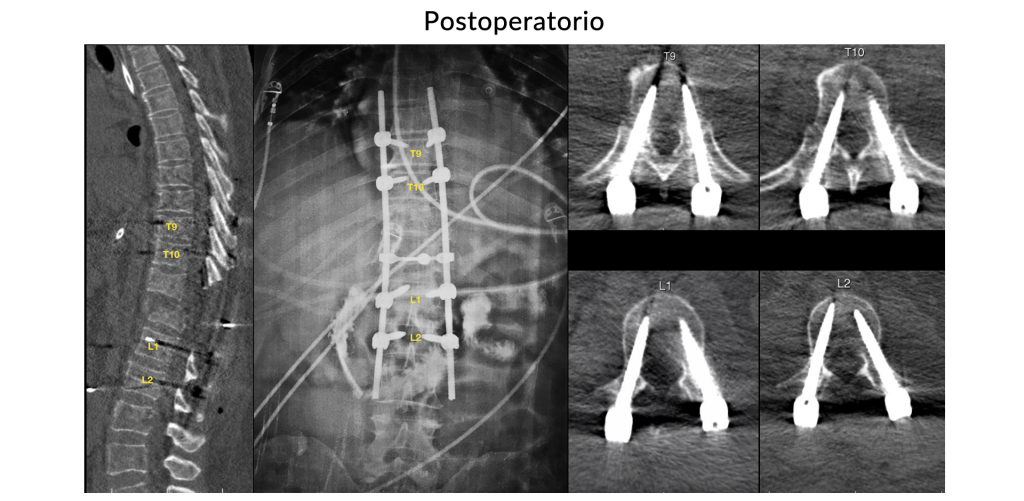

Trauma Raquimedular Torácico